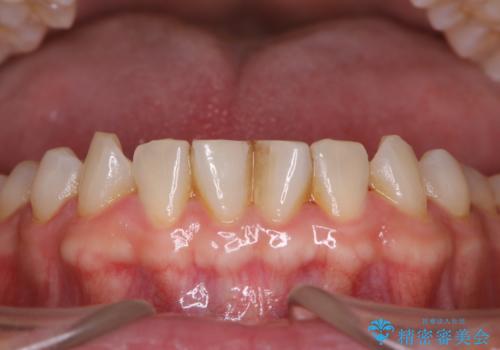

治療途中

お口全体に、歯垢・歯石が付着していたため、自費クリーニング(PMTC)60分コースを行い、徹底的に除去しました。

日々の磨き残しなどをそのまま放置すると、細菌が固まり硬い歯石になります。

歯石になってしまうと、とても硬く、歯ブラシで取り除くことが出来なくなります。